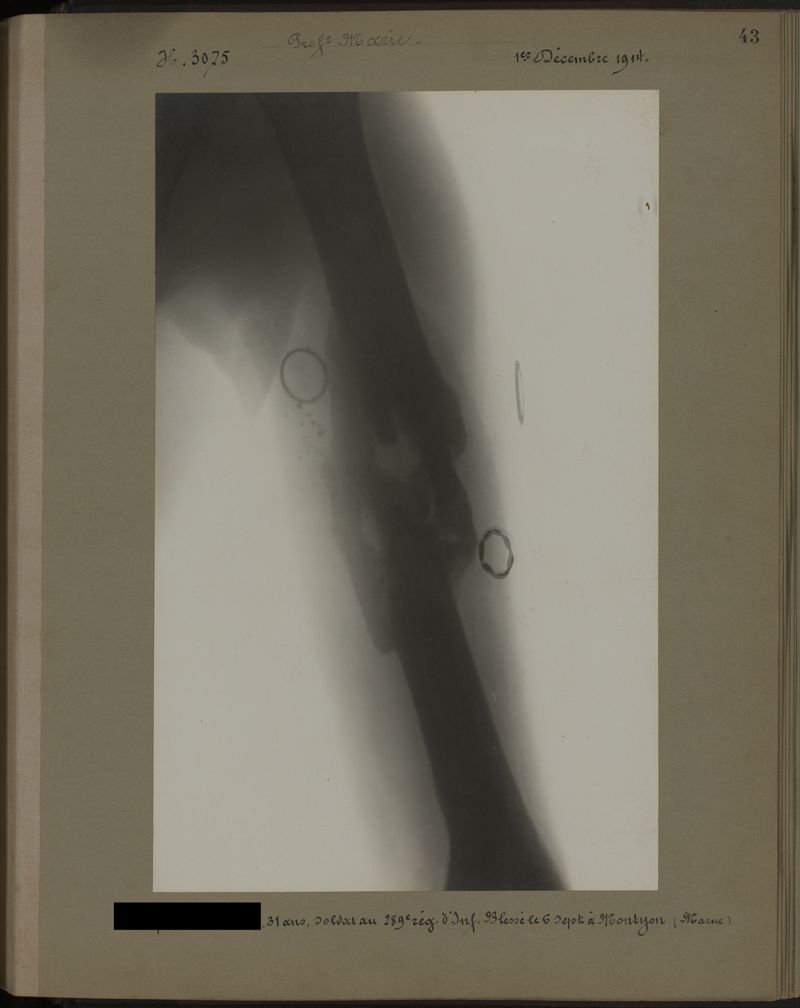

Deux albums de radiographies de la Première Guerre mondiale. Collection du laboratoire central de radiographie de la Salpêtrière. Deuxième album.

1915.